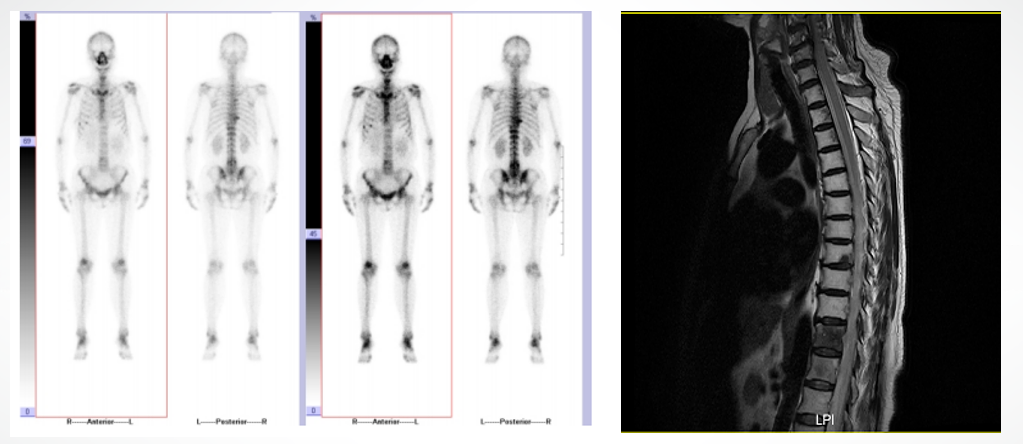

2022-01-23肝脏增强MR示:肝IV段及右叶见多发结节状、团片状长T1、长T2信号灶,DWI及ADC示弥散受限,增强扫描见边缘强化或结节状强化,较大者位于IV段,大小约29mm×21mm。附见:脊柱及两侧肋骨多发异常强化灶,考虑转移。

全身骨显像提示:全身多发骨转移性肿瘤。

胸椎磁共振平扫提示:胸椎及附件多发长T2信号改变,结合病史,符合胸椎及附件多发转移瘤表现。